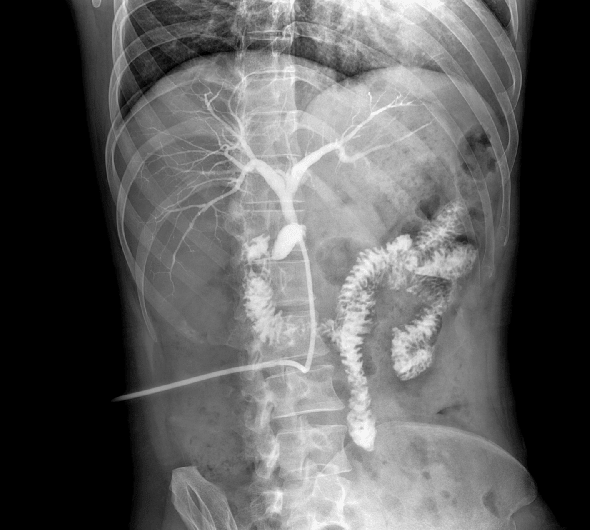

临床图像